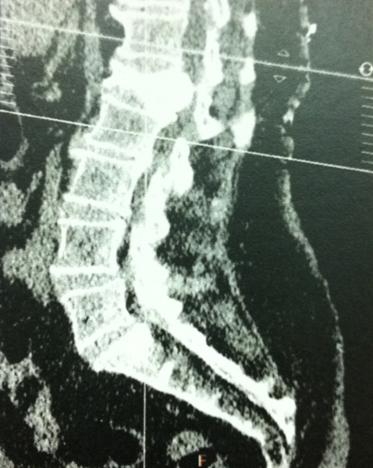

Mme S., 68 ans, a présenté une fracture vertébrale de L1. Le bilan biologique a conclu à une ostéoporose post-ménopausique.

Devant la persistance de douleurs dorsolombaires à 3 mois, malgré le traitement médical bien conduit, une cimentoplastie de L1 a été pratiquée.

Dans les suites, Mme S. a ressenti des paresthésies dans le territoire de L1 à droite. Une tomodensitométrie est pratiquée.